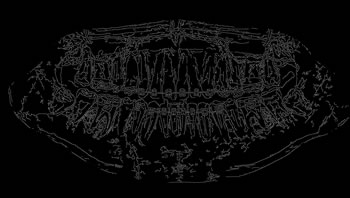

To thoroughly benchmark the methods studied here, the 1,500 images were distributed among 10 categories. The images were named, using whole numbers, in sequential order by category, aiming at not identifying the patients in the study. The process of categorizing the images was performed manually, selecting images individually, counting tooth by tooth, as well as verifying structural characteristics of the teeth. The images were classified according to the variety of structural characteristics of the teeth (see Table 5). Finally, the images were cut out to disregard non-relevant information (white border around the images and part of the spine) generated by the orthopantomograph device. After the clipping process, there was a change in the size of the images to 1991 ×\times 1127 pixels, but without affecting the objects of interest (teeth), as shown in Figure 2. The cropped images were saved on the new dimension to be used in the following stages, which will be presented in the next sections. Figure 3 shows an X-ray image corresponding to each of the categories of our data set.

Refer to caption

Figure 2: Example of the clipping and resizing of the data set images of the present work.